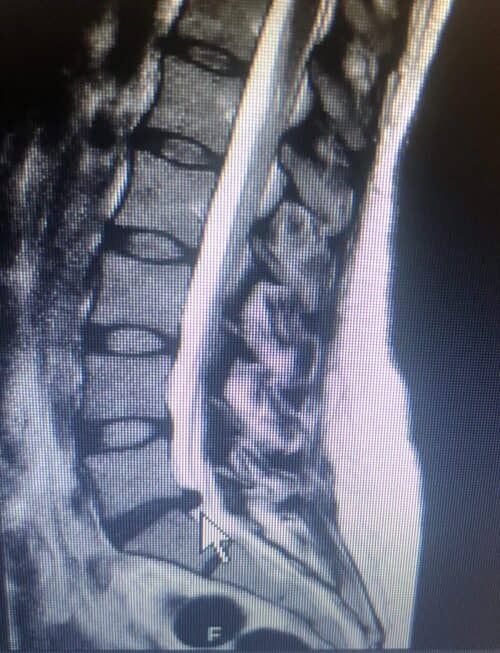

Resonancia magnética

En esta foto se aprecia como se ve una hernia discal en una resonancia en la L5-S1

La resonancia magnetica de una hernia lumbar (o RM por sus siglas) es una técnica de imagen utilizada comúnmente para visualizar con detalle los tejidos blandos de la espina dorsal, incluidos los discos intervertebrales. Esta prueba puede proporcionar información crucial sobre la presencia y extensión de una hernia discal.